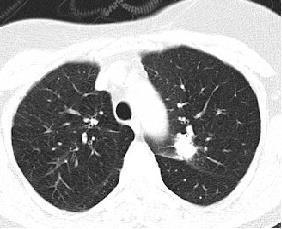

TheproposedsystemismethodicallytestedusingdifferentlungnoduleCTimage.

Fig.1CTscansLungNoduleImages